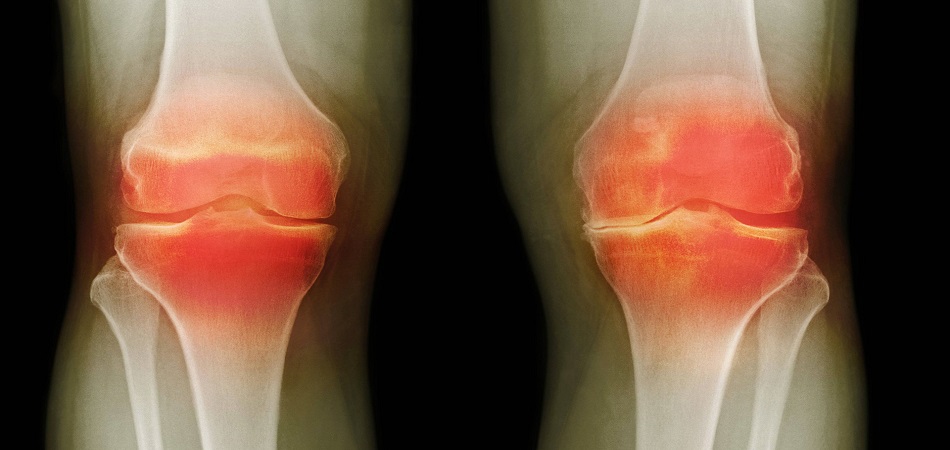

Femme de 54 ans. Son articulation est entièrement restaurée. La durée du traitement : 14 jours :

Traitement de l'articulation de la hanche d'un patient âgé de 44 ans. La douleur atroce qui a torturé le patient pendant 2 ans, a été complètement guérie :

Restauration de l'articulation du coude. Patiente, 31 ans. Durée du traitement par la Marukaya Cream : 12 jours. Son articulation est entièrement restaurée :